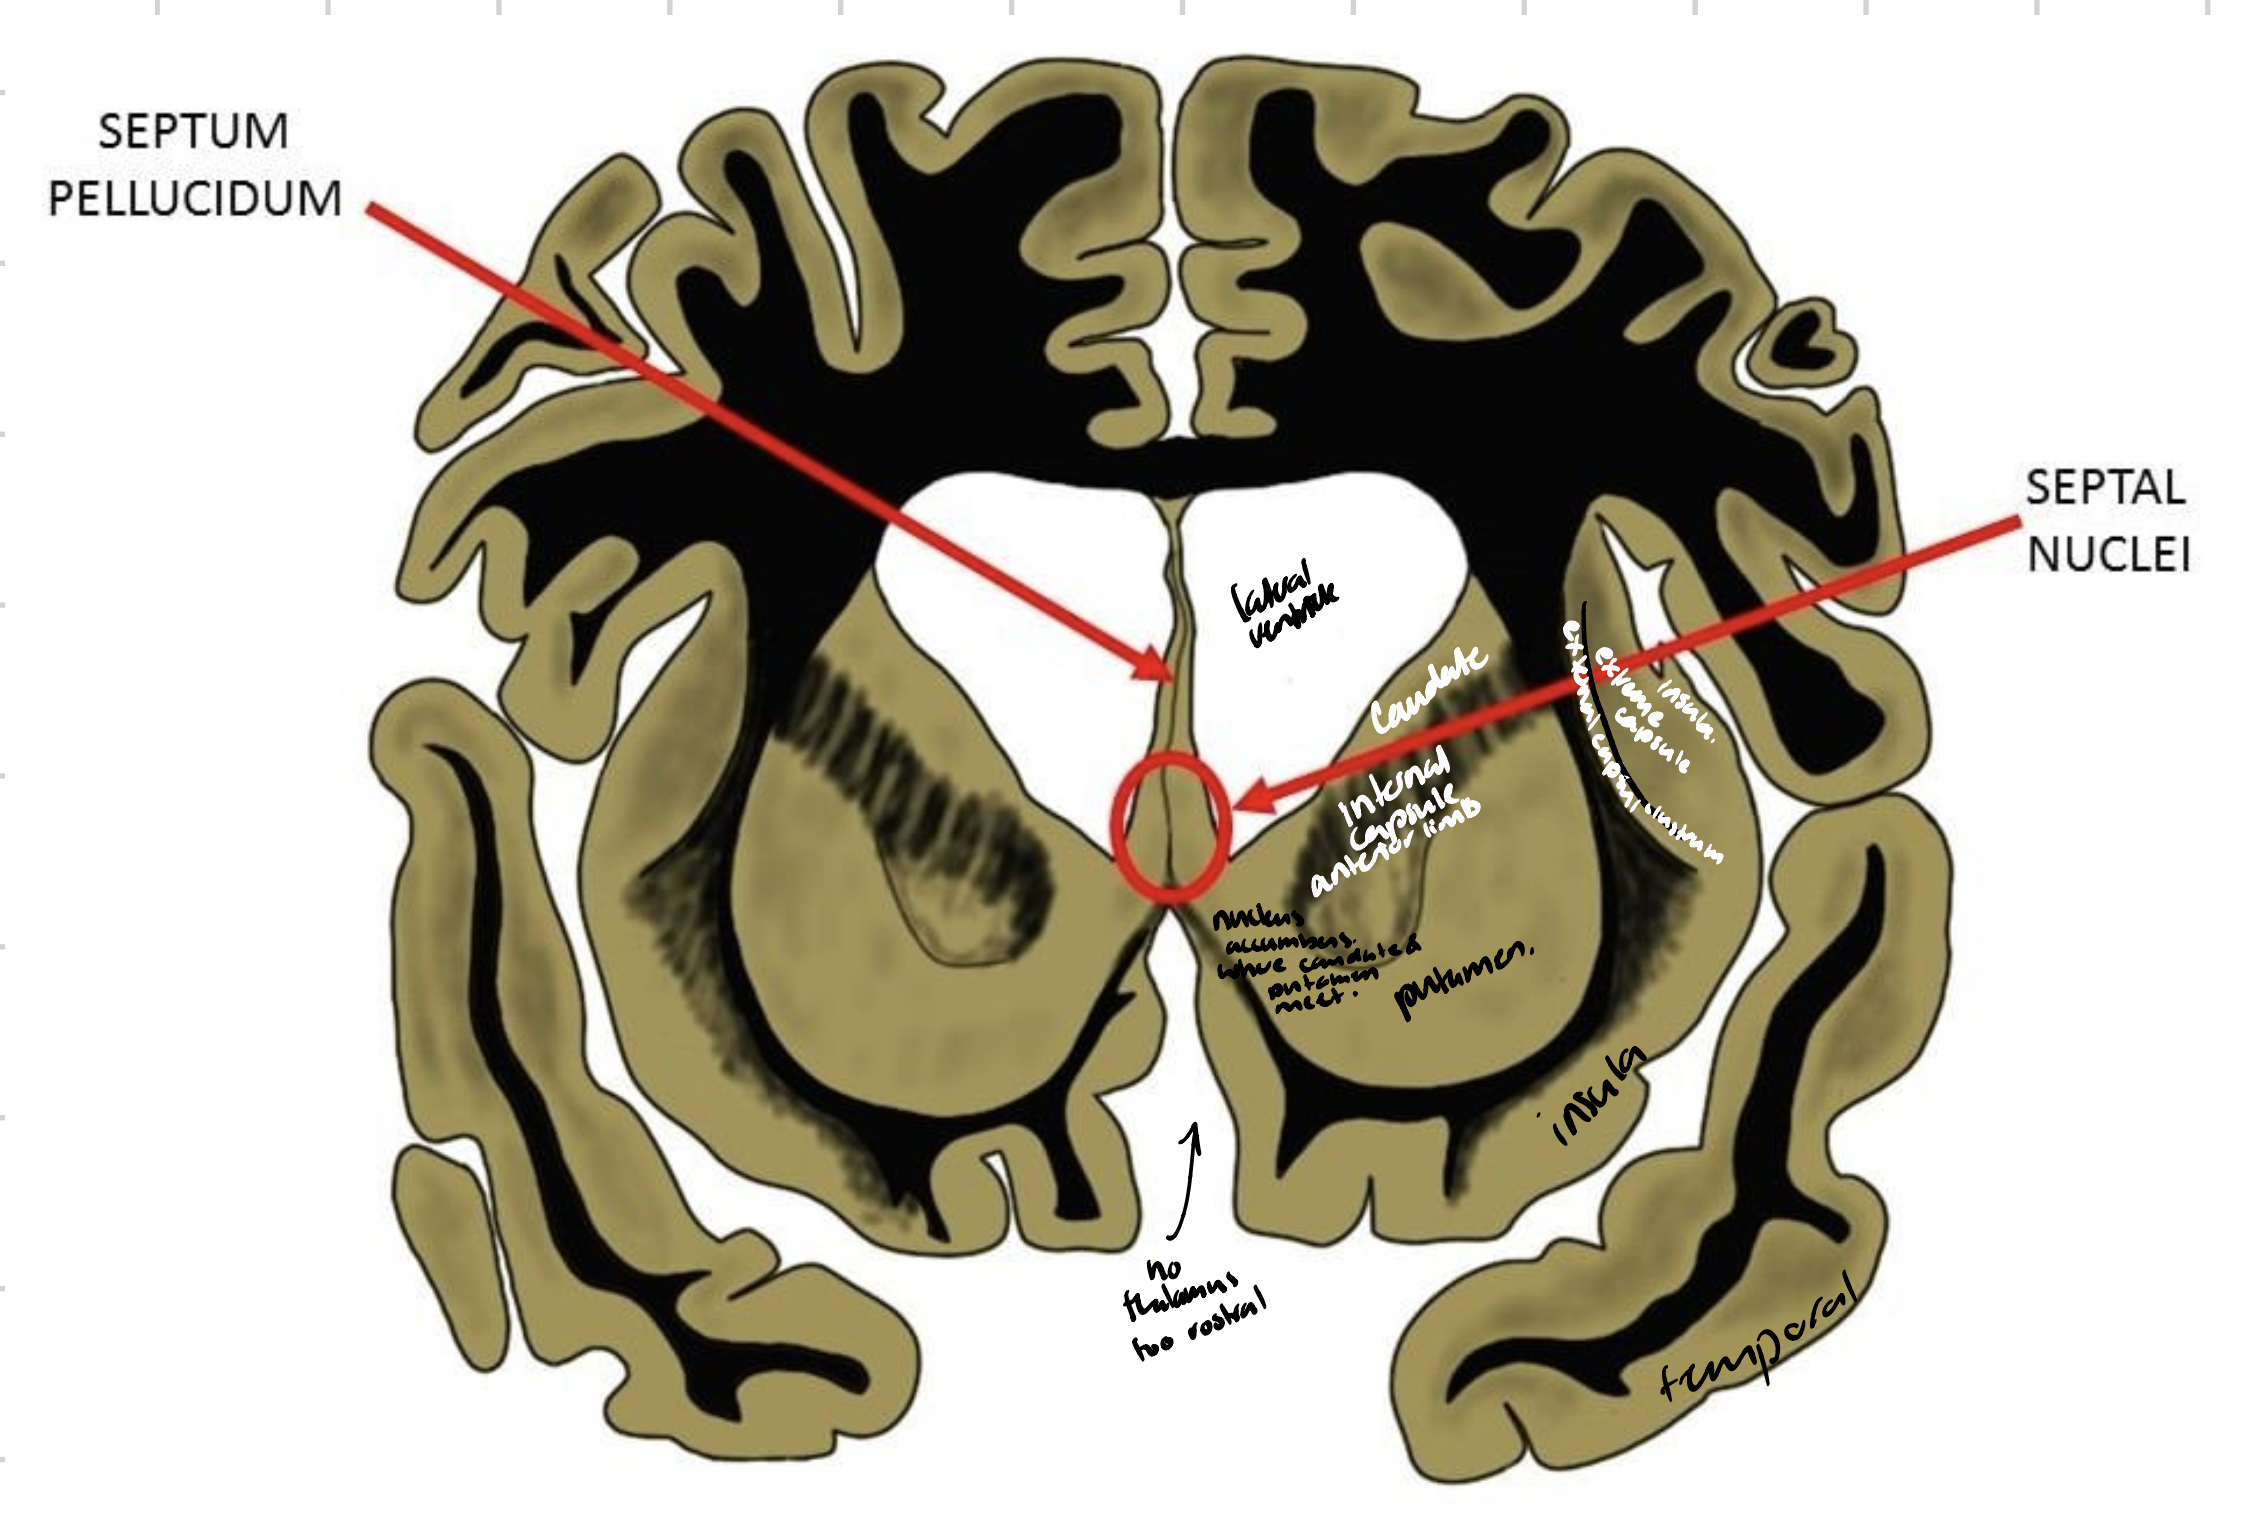

Head, body and tail of caudate nucleus - top

Putamen - middle

Nucleus accumbens - bottom

Stria terminalis - between caudate nucleus and lateral ventricles

The tail of the caudate nucleus ends at which structure?

Amygdala

Which structure is found between the caudate nucleus and the lateral ventricle?

Septal nuclei

Lenticular nucleus

Internal capsule

Thalamus

External capsule

Claustrum

Extreme capsule

Insula

Head and tail of the caudate nucleus

Globus pallidus

Putamen

External capsule

Claustrum

Extreme capsule

Body and splenium of corpus callosum

Anterior and posterior horns of lateral ventricles

Choroid plexus

Septum pellucidum

Fornix

Insula

Lateral fissure